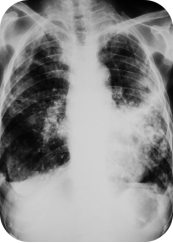

以上是他的胸部CT影像,主要表现为左下肺炎症,片絮影+磨玻璃影。

肺部感染的影像学特征

混合性密度影与胸腔积液

40%病例出现磨玻璃影与实变影共存,部分结节中央可见液化坏死;30%伴单侧渗出性胸腔积液,积液分析呈渗出性但培养阴性,此表现易误诊为脓胸。